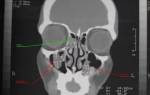

Обычно после проведения рентгена никаких вопросов не остается. Но, если ситуация все еще остается не проясненной, назначают проведение компьютерной томографии. Это очень информативный метод диагностики. Благодаря КТ удается в деталях рассмотреть все структурные изменения пазух, выявить воспаление, уплотнение, деформацию и т. д.

- Пристеночное затемнение на снимке. Его можно заметить на рентгенограмме. Для подтверждения диагноза снимки делают минимум в двух проекциях. Разросшийся эпителий напоминает темные асимметричные пятна. Помимо этого, применяют КТ и МРТ.

- Рентгенография – информативный диагностический метод. Дополнительно применяют проведение анализов, сбор анамнеза и оценку боли.